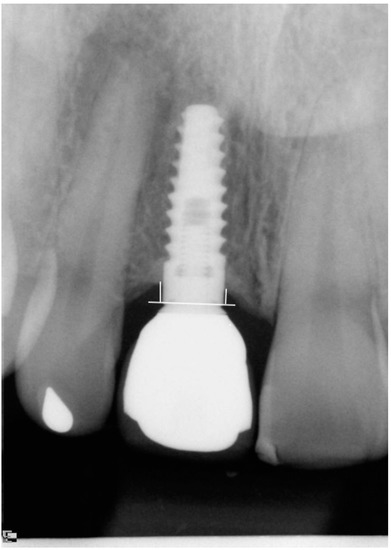

A Randomized Clinical Trial Comparing Immediate Loading and Delayed Loading of Single-Tooth Implants: 5-Year Results

3.1. Marginal Bone Loss and Papilla Index